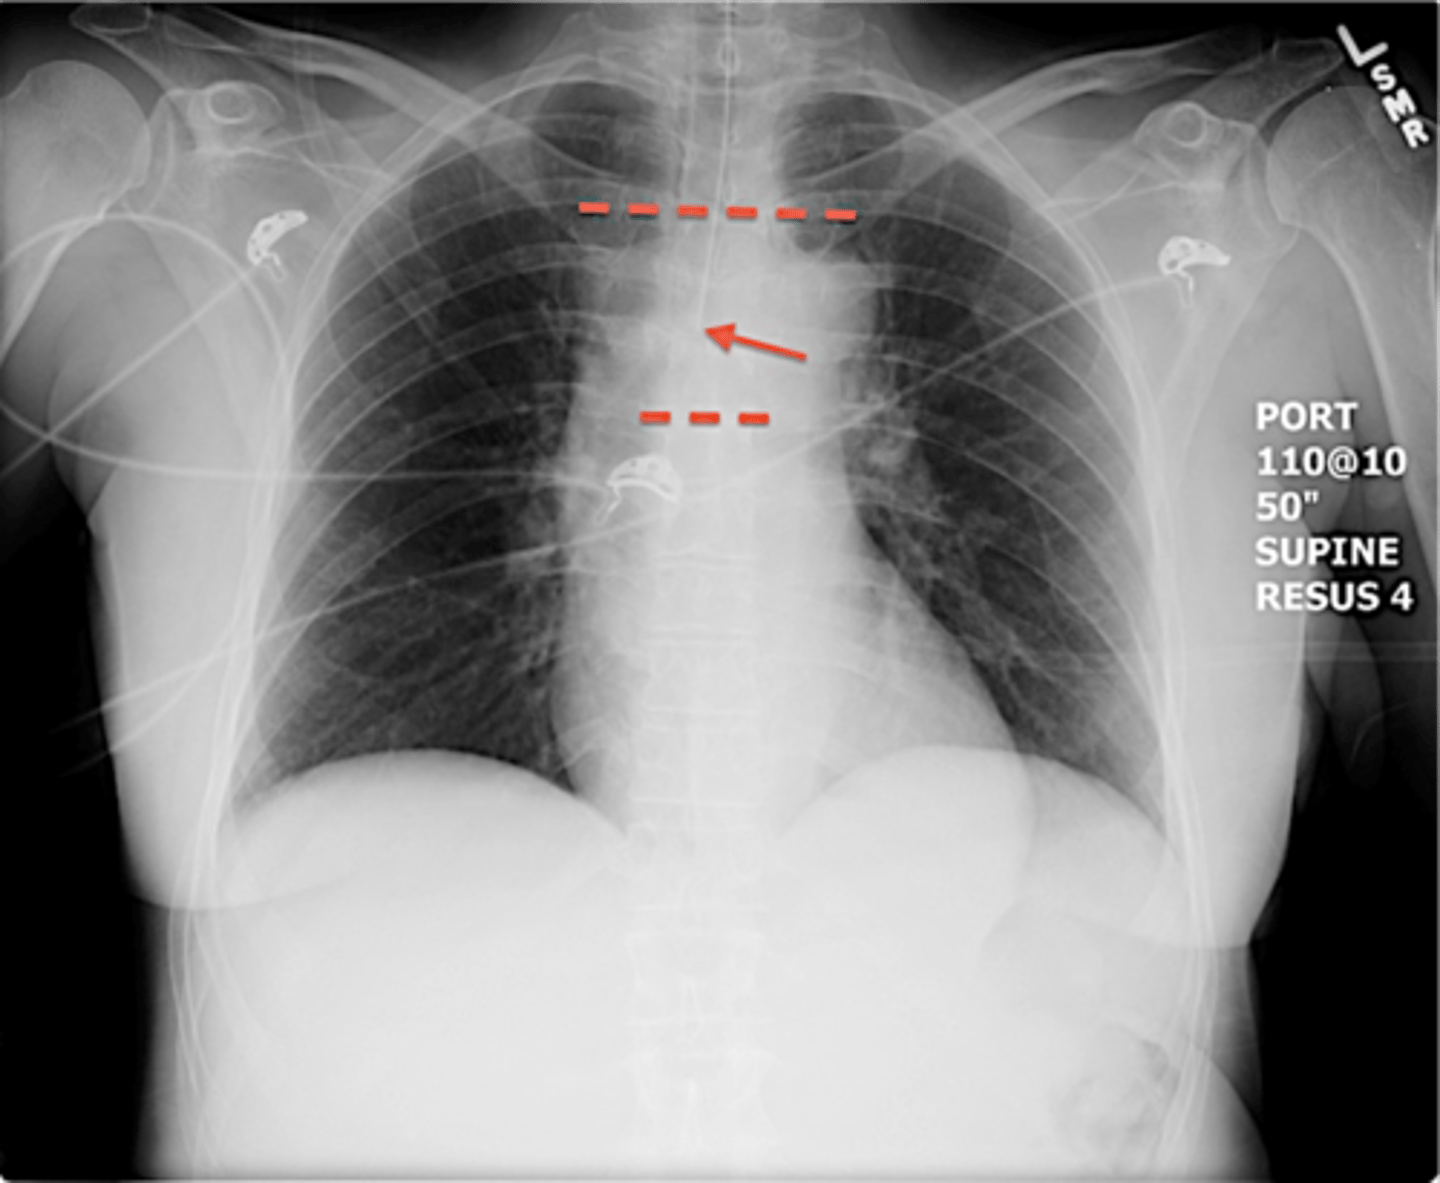

-3-5cm above carina

-middle of carina and clavicles

ET tube